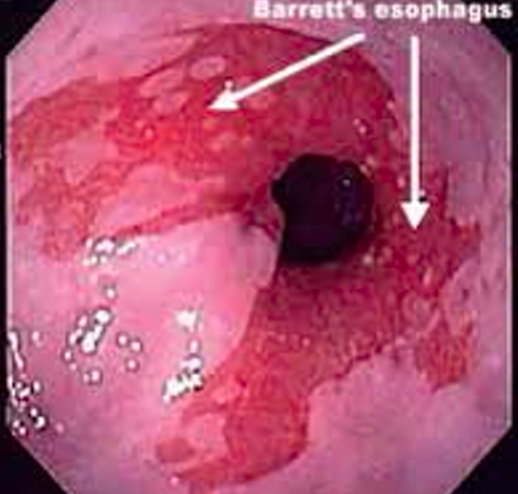

What is the pathophysiology of Barret’s oesophagus and how does it present?

- Metaplasia of the lower oesophagus from stratified squamous to simple columnar

How do you investigate and diagnose a suspected case of Barrett’s oesophagus?

- Histologically by taking a biopsy during OGD for chronic or resistant GORD

- Severity depends on amount of dysplasia and the length (Prague classification)